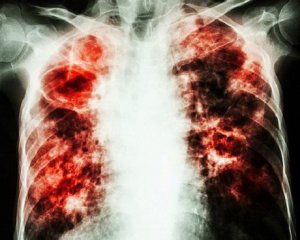

Учені дослідили останки єпископа шведсько-датського походження Педера Йенсена Вінструпа, померлого 1679 року. У його легенях знайшли невеликі затвердіння, що виявилися наслідком перенесеного туберкульозу, повідомляє "Вокруг света".

З кальцитових освітів вдалося витягти геном палички Коха, що називають надзвичайною удачею для таких давніх поховань. Оскільки вчені знали точну дату смерті єпископа, то змогли простежити походження збудника.

За їхніми висновками, туберкульозна паличка відокремилася від загального предка близько 2-6 тис. років тому. Це руйнує прийняту нині гіпотезу, що хвороба супроводжує людство з часів виходу з Африки сотні тисяч років тому.